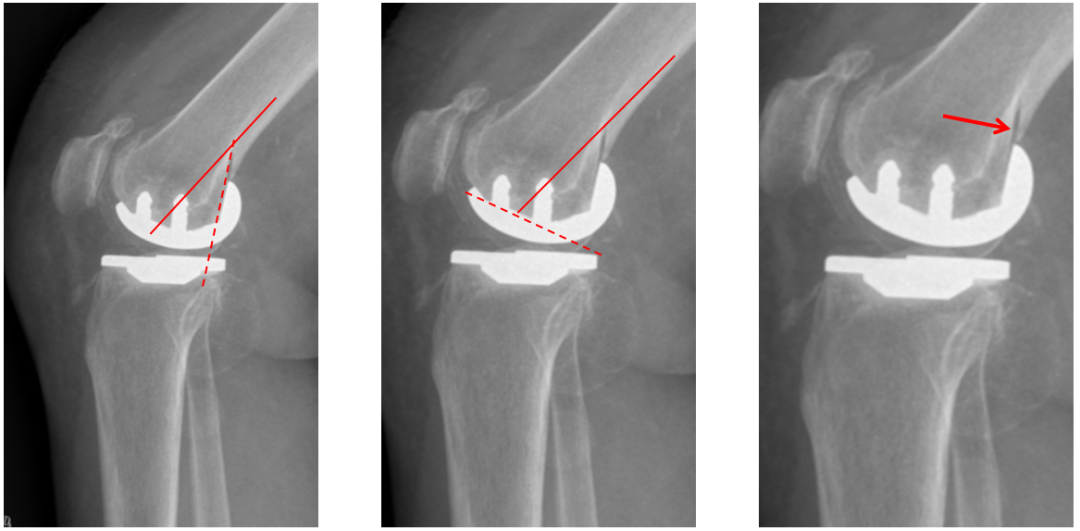

股骨假体后倾不足

侧位股骨假体位置:股骨假体后倾5°,后髁包容不足。

股骨假体过屈(皮质损伤)

侧位股骨假体位置:股骨远端后倾15°截骨,导致后髁115°截骨,后侧皮质损伤。

股骨假体过伸

侧位股骨假体位置:股骨远端前倾10°截骨,导致股骨股骨后髁截骨与股骨髓腔中心轴平行,股骨假体过伸。